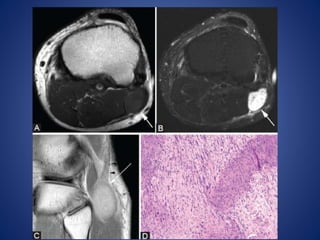

• #21 Gastrocnemius ganglion. A 45-year-old male with knee pain. Sagittal PDW image (A) demonstrates lobulated lesion (arrows) at insertion of medial head of gastrocnemius that is hyperintense on sagittal (B) and coronal (C) T2W fat-saturated images